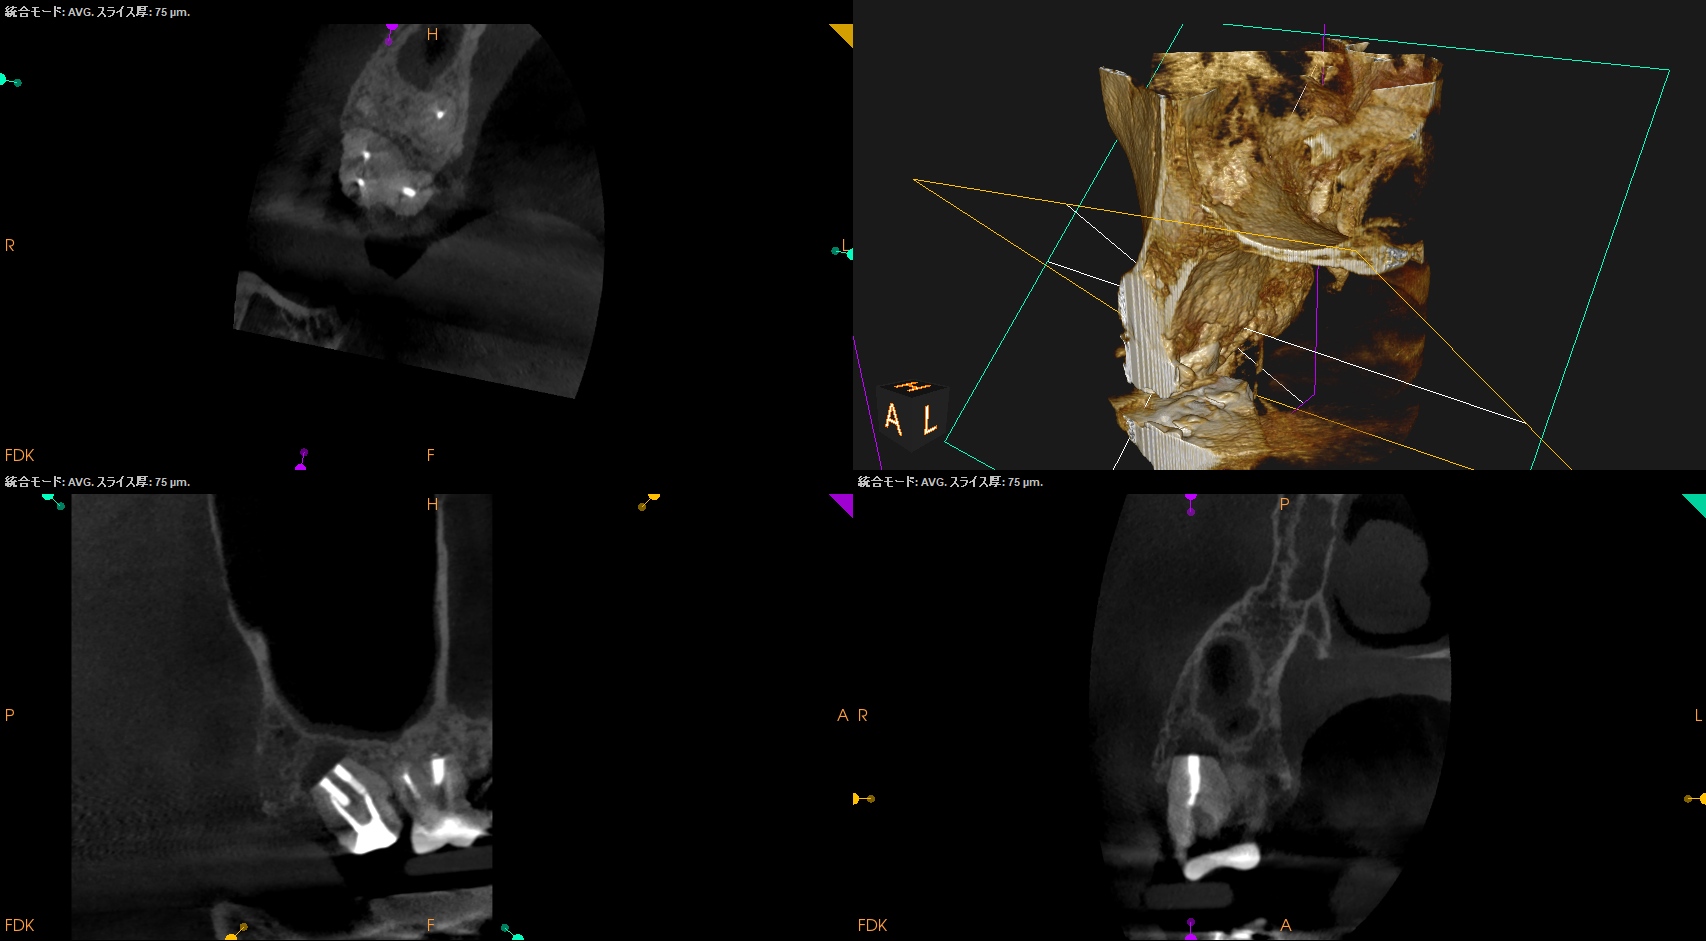

以前の治療の経過観察。

あれからさらに1ヶ月が経過した。

#2 Intentional Replantation 2M recall(2025.10.1)

痛みはないが若干、違和感がある程度に症状は軽減した。

臨床症状はないのでかかりつけ医の先生にはプロビジョナルレストレーションの装着を依頼した。